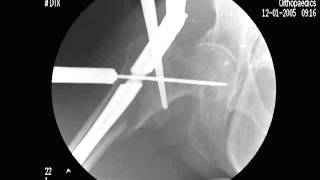

- Stryker Gamma Nail to treat a hip intertrochanteric fracture

- Intramedullary Nailing (Gamma Nail 3rd Generation)

Demonstration of Gamma Nail 3rd Generation.Watch Now

- TROCHANTERIC FRACTURE GAMMA NAIL- G , OS G3

Gamma Nail Fixation